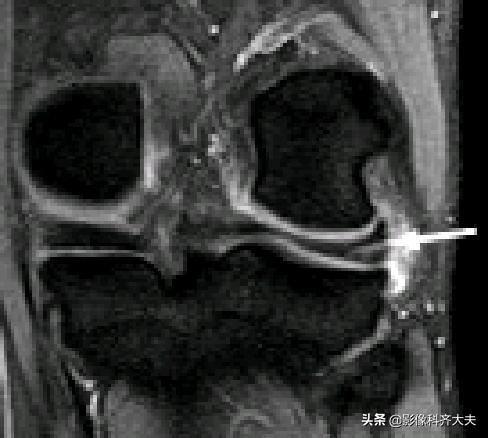

容易误诊为半月板损伤的正常解剖结构

后股板韧带:

内侧半月板后角上隐窝: